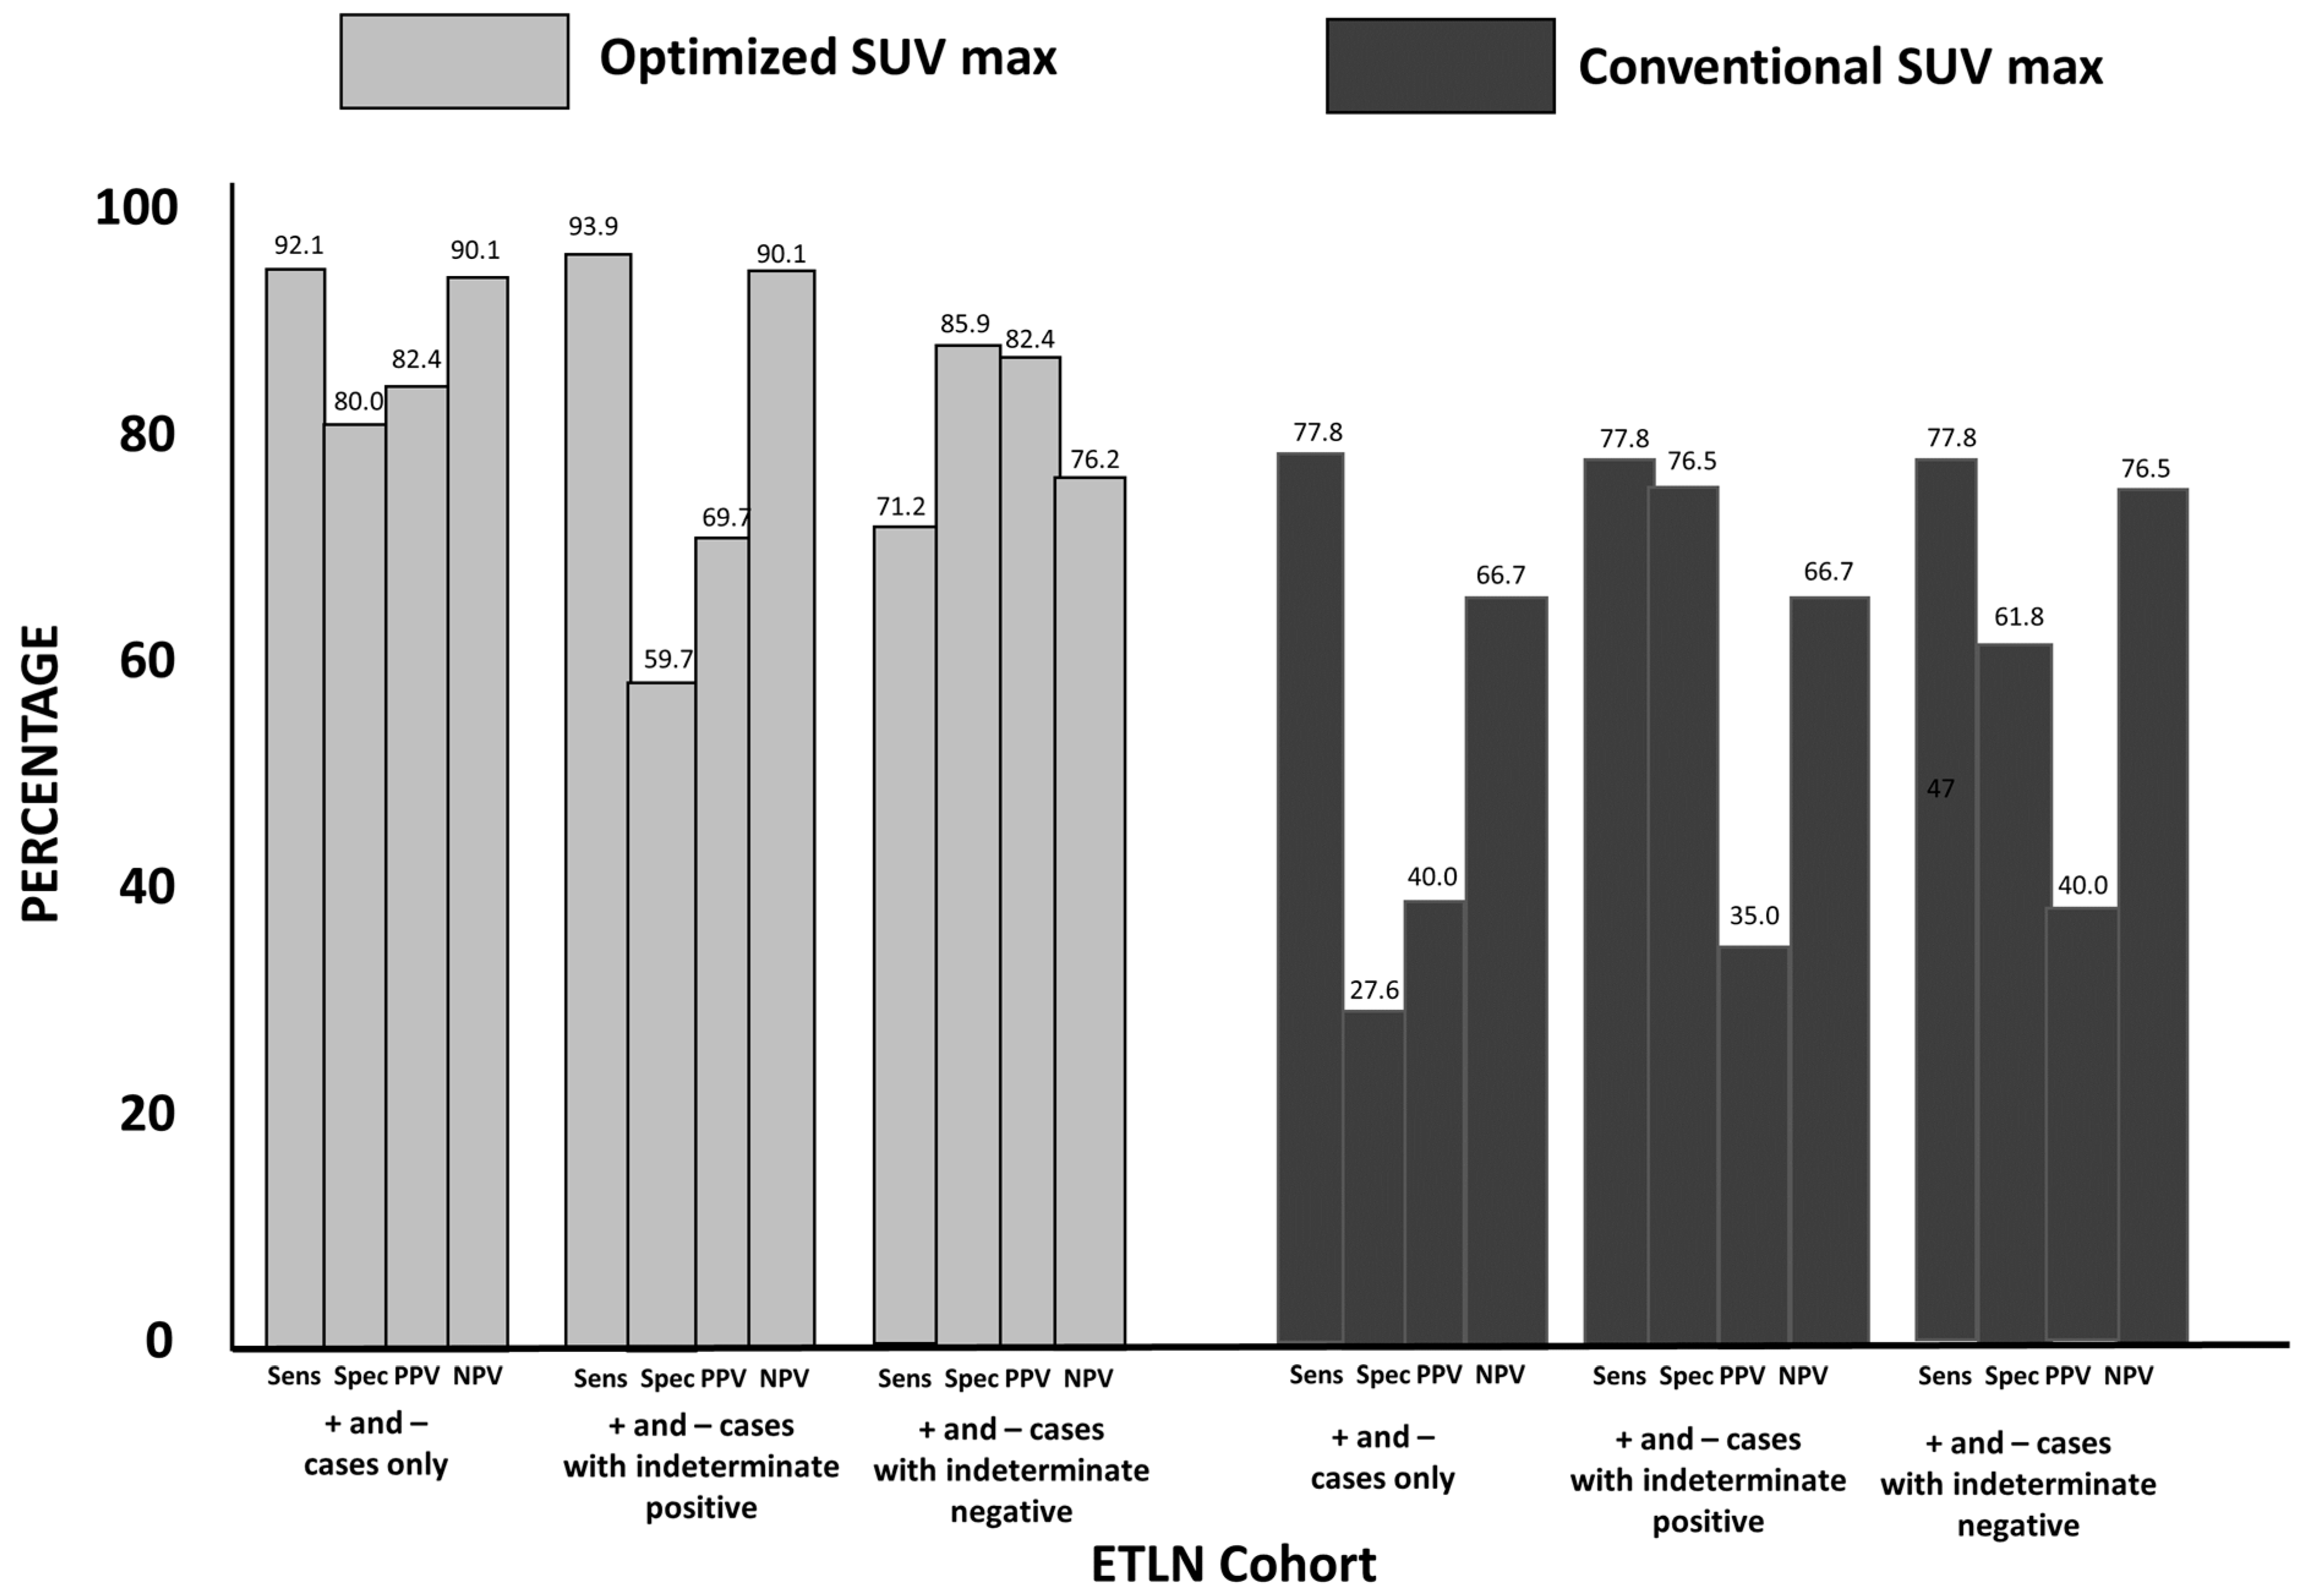

3.3. Group 2: ETLN Cohort